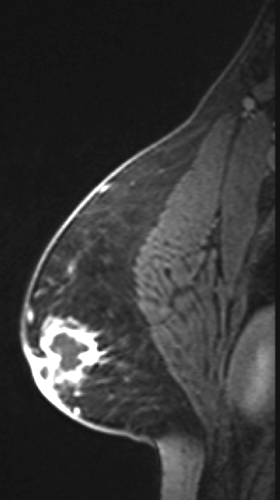

A 30-year-old Japanese male presented with pain and swelling of the left breast of seven days duration. There was no past history of similar complaints or any other relevant medical history. Physical examination revealed a 3.0x3.0 cm palpable lump with redness of the skin in the left subareolar region (Figure 1). There was no abnormal nipple discharge. Sonography revealed a complex, hypoechoic subareolar mass with a heterogeneous hypoechoic internal echo containing complex fluid and internal vascularity (Figure 2). Magnetic resonance imaging showed a ring-enhancing mass without wash out with central necrosis below the left nipple (Figure 3), suggesting subareolar abscess. A core needle biopsy was performed, and histological findings revealed granulation tissue with the infiltration of numerous neutrophils, a finding that was compatible subareolar abscess (Figure 4). Ultrasound-guided drainage and antibiotic therapy (cefcapene pivoxil) were prescribed. Culture showed the growth of Propionibacterium acnes. The patients required incisional drainage through subareolar incision. No recurrence has been seen for sixteen months.

Figure 3: Magnetic resonance imaging revealed a ring-enhancing mass without wash out below the left nipple as characteristic finding in cases of subareolar abscess.

We report herein an extremely rare case of subareolar abscess in the male breast. Male subareolar abscess is a localized infection secondary to ductal ectasia, chronic obstruction, and inflammation [1][6]. Smoking is recognized as an aggravation factor, and almost 70% of patients smoked more than 10 cigarettes a day [6][7]. In this case, the patient was a smoker. Common clinical features include pain, nipple swelling, and nipple discharge [1]. On sonography, the abscess usually appears as an incompletely circumscribed mass containing complex fluid (Figure 1). Doppler imaging often shows accentuation of peripheral vascularity with sparse-to-absent internal flow. However, occasionally abscesses may have accentuated internal flow, making the diagnosis of infection less certain and therefore requiring tissue sampling. In our case, core needle biopsy was performed [1]. However, MRI scan may be useful for reaching a differential diagnosis of subareolar abscess. MRI scan revealed a ring-enhancing mass without wash out below the left nipple, which is a characteristic finding in cases of abscess. This case indicates the importance of MRI in differentiating between subareolar abscess and malignancy in the male breast. Familiarity with the features of the male subareolar abscess including MRI findings allows for accurate imaging and make it possible to avoid unnecessary and often invasive treatment.